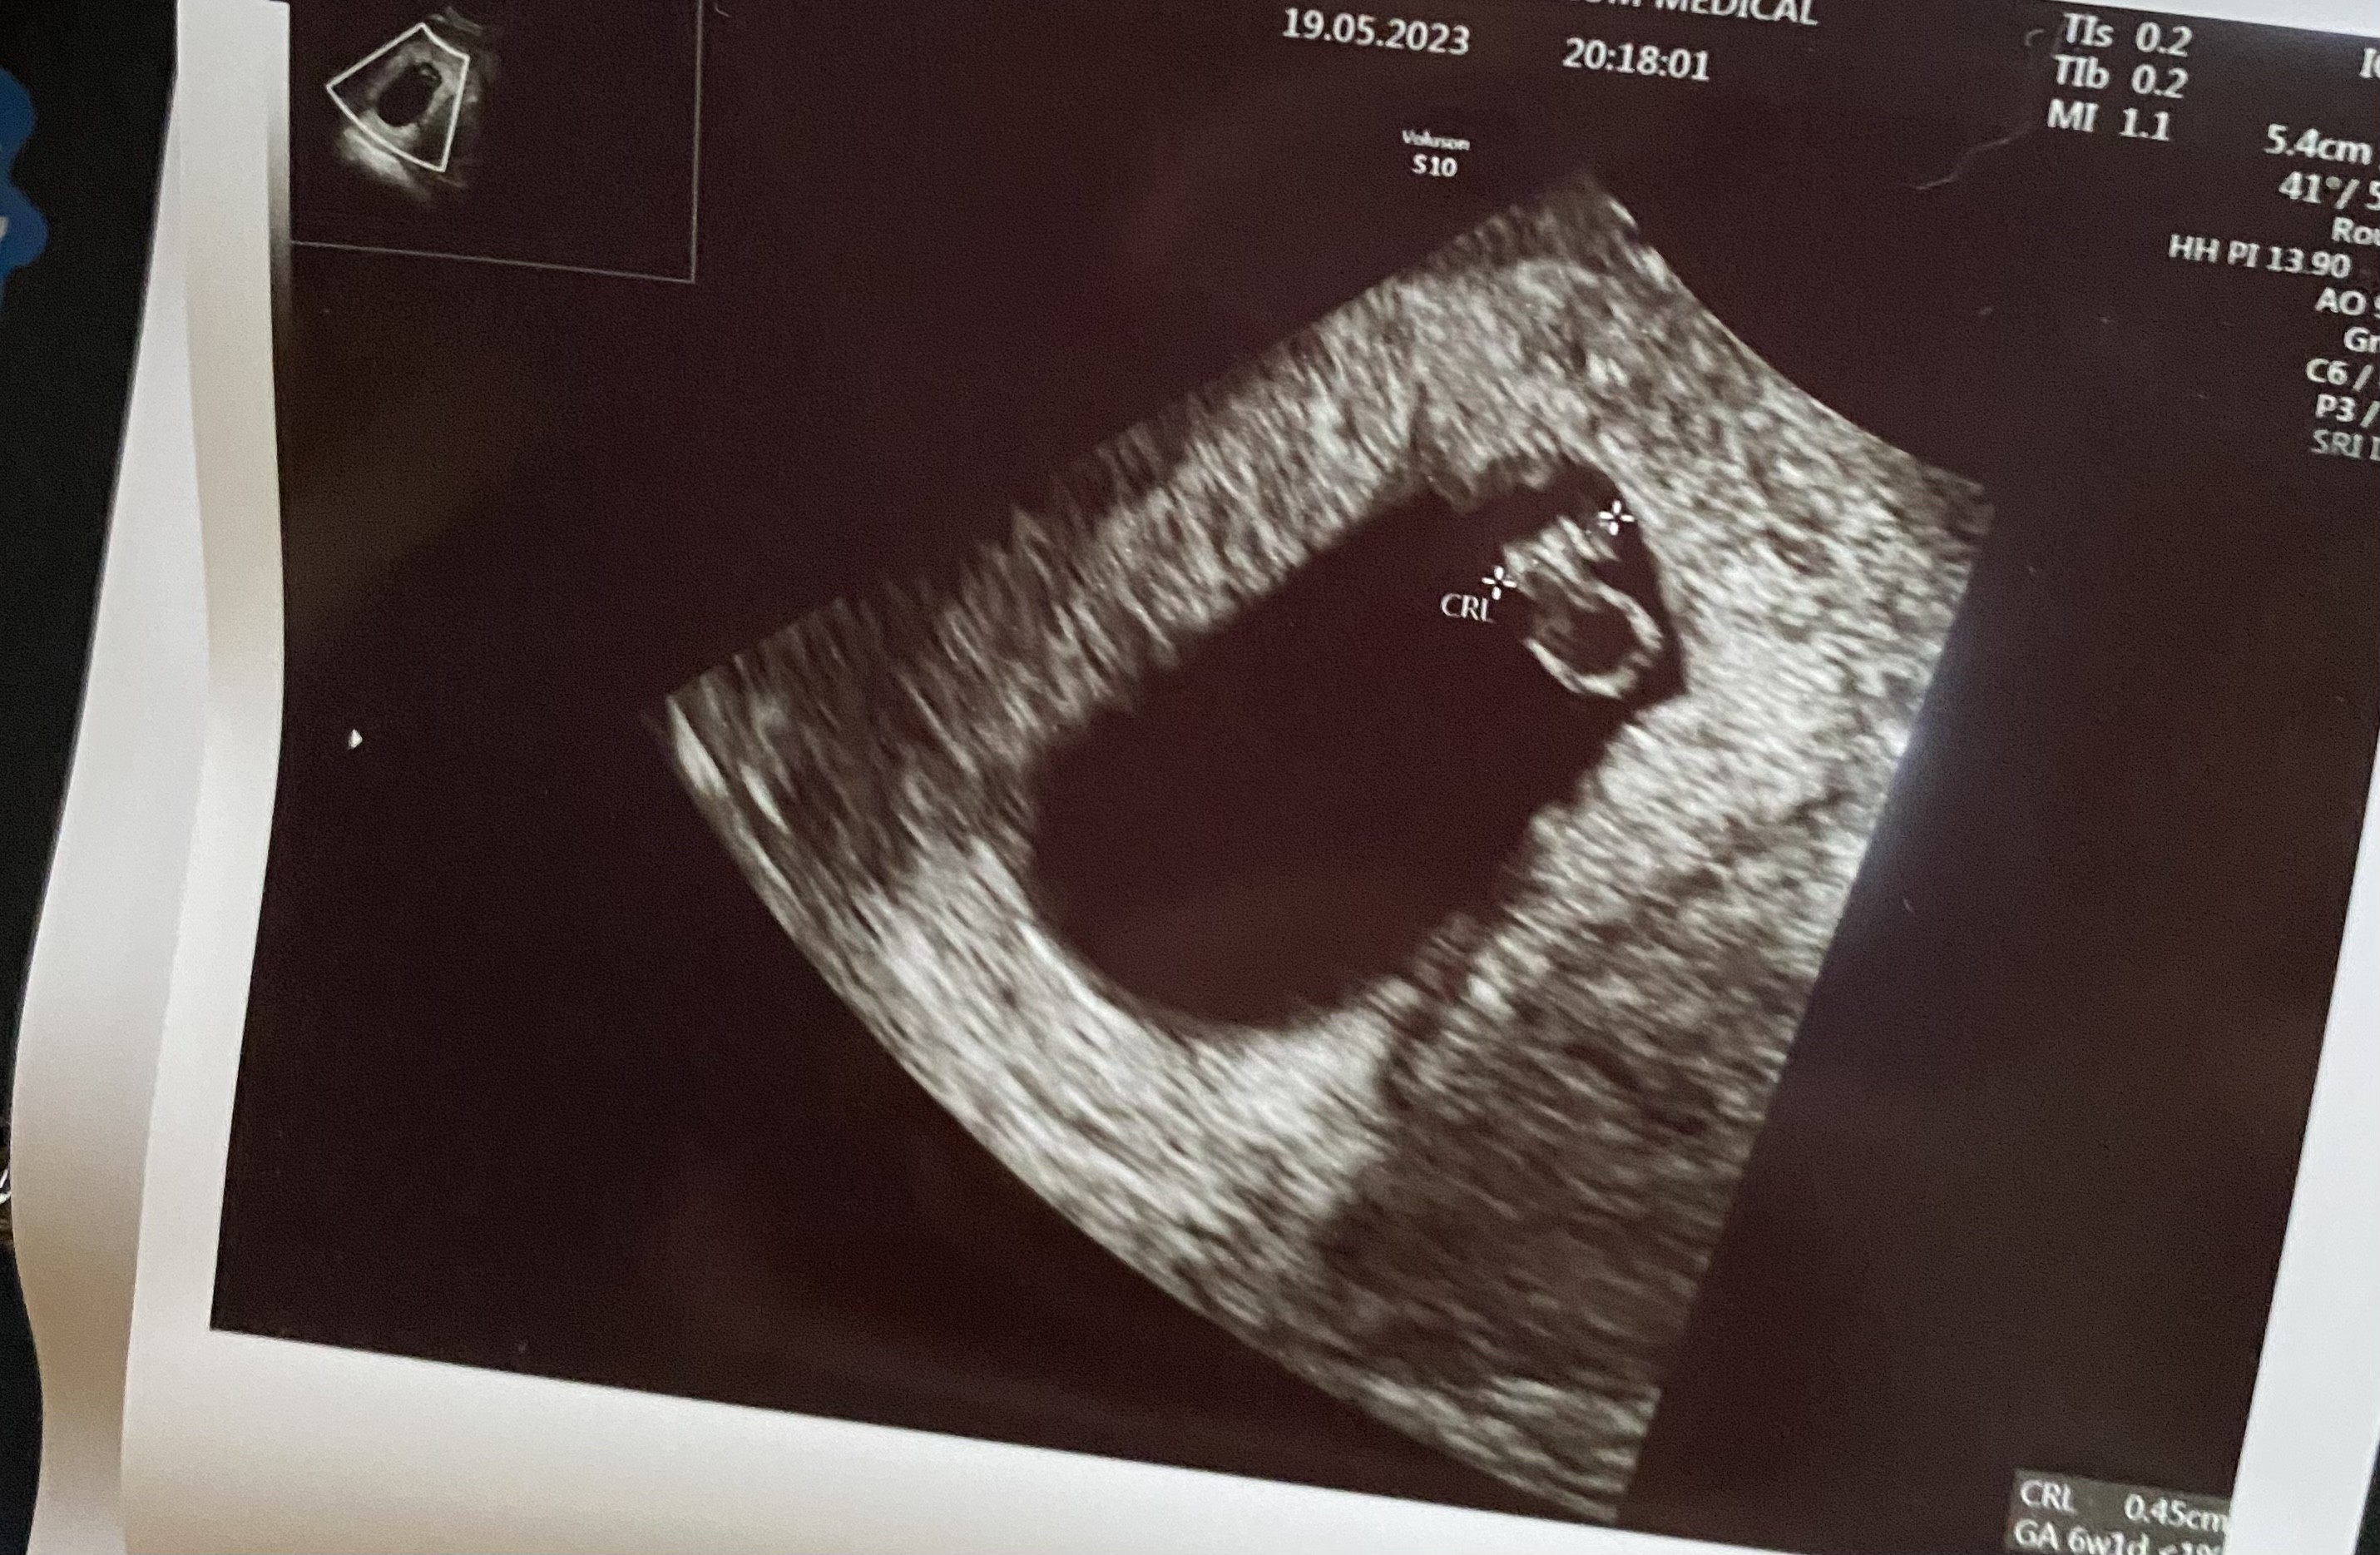

Beta 11 maj 6,7 mIU

Beta 13 maj 36,2 mIU

Beta 19 maj 749,8 mIU

No juz nie ma odwrotu